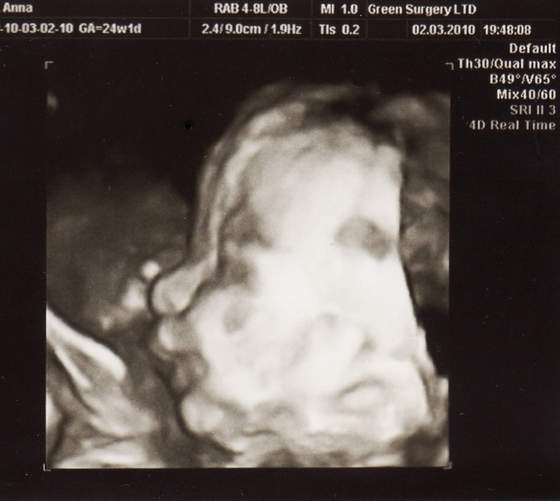

ale lekarka mnie uspokoiłanadika wstydziosze z Natanka:-)Cudeńko z piękną wagąA co lekarz mówił na tą pępowinę?